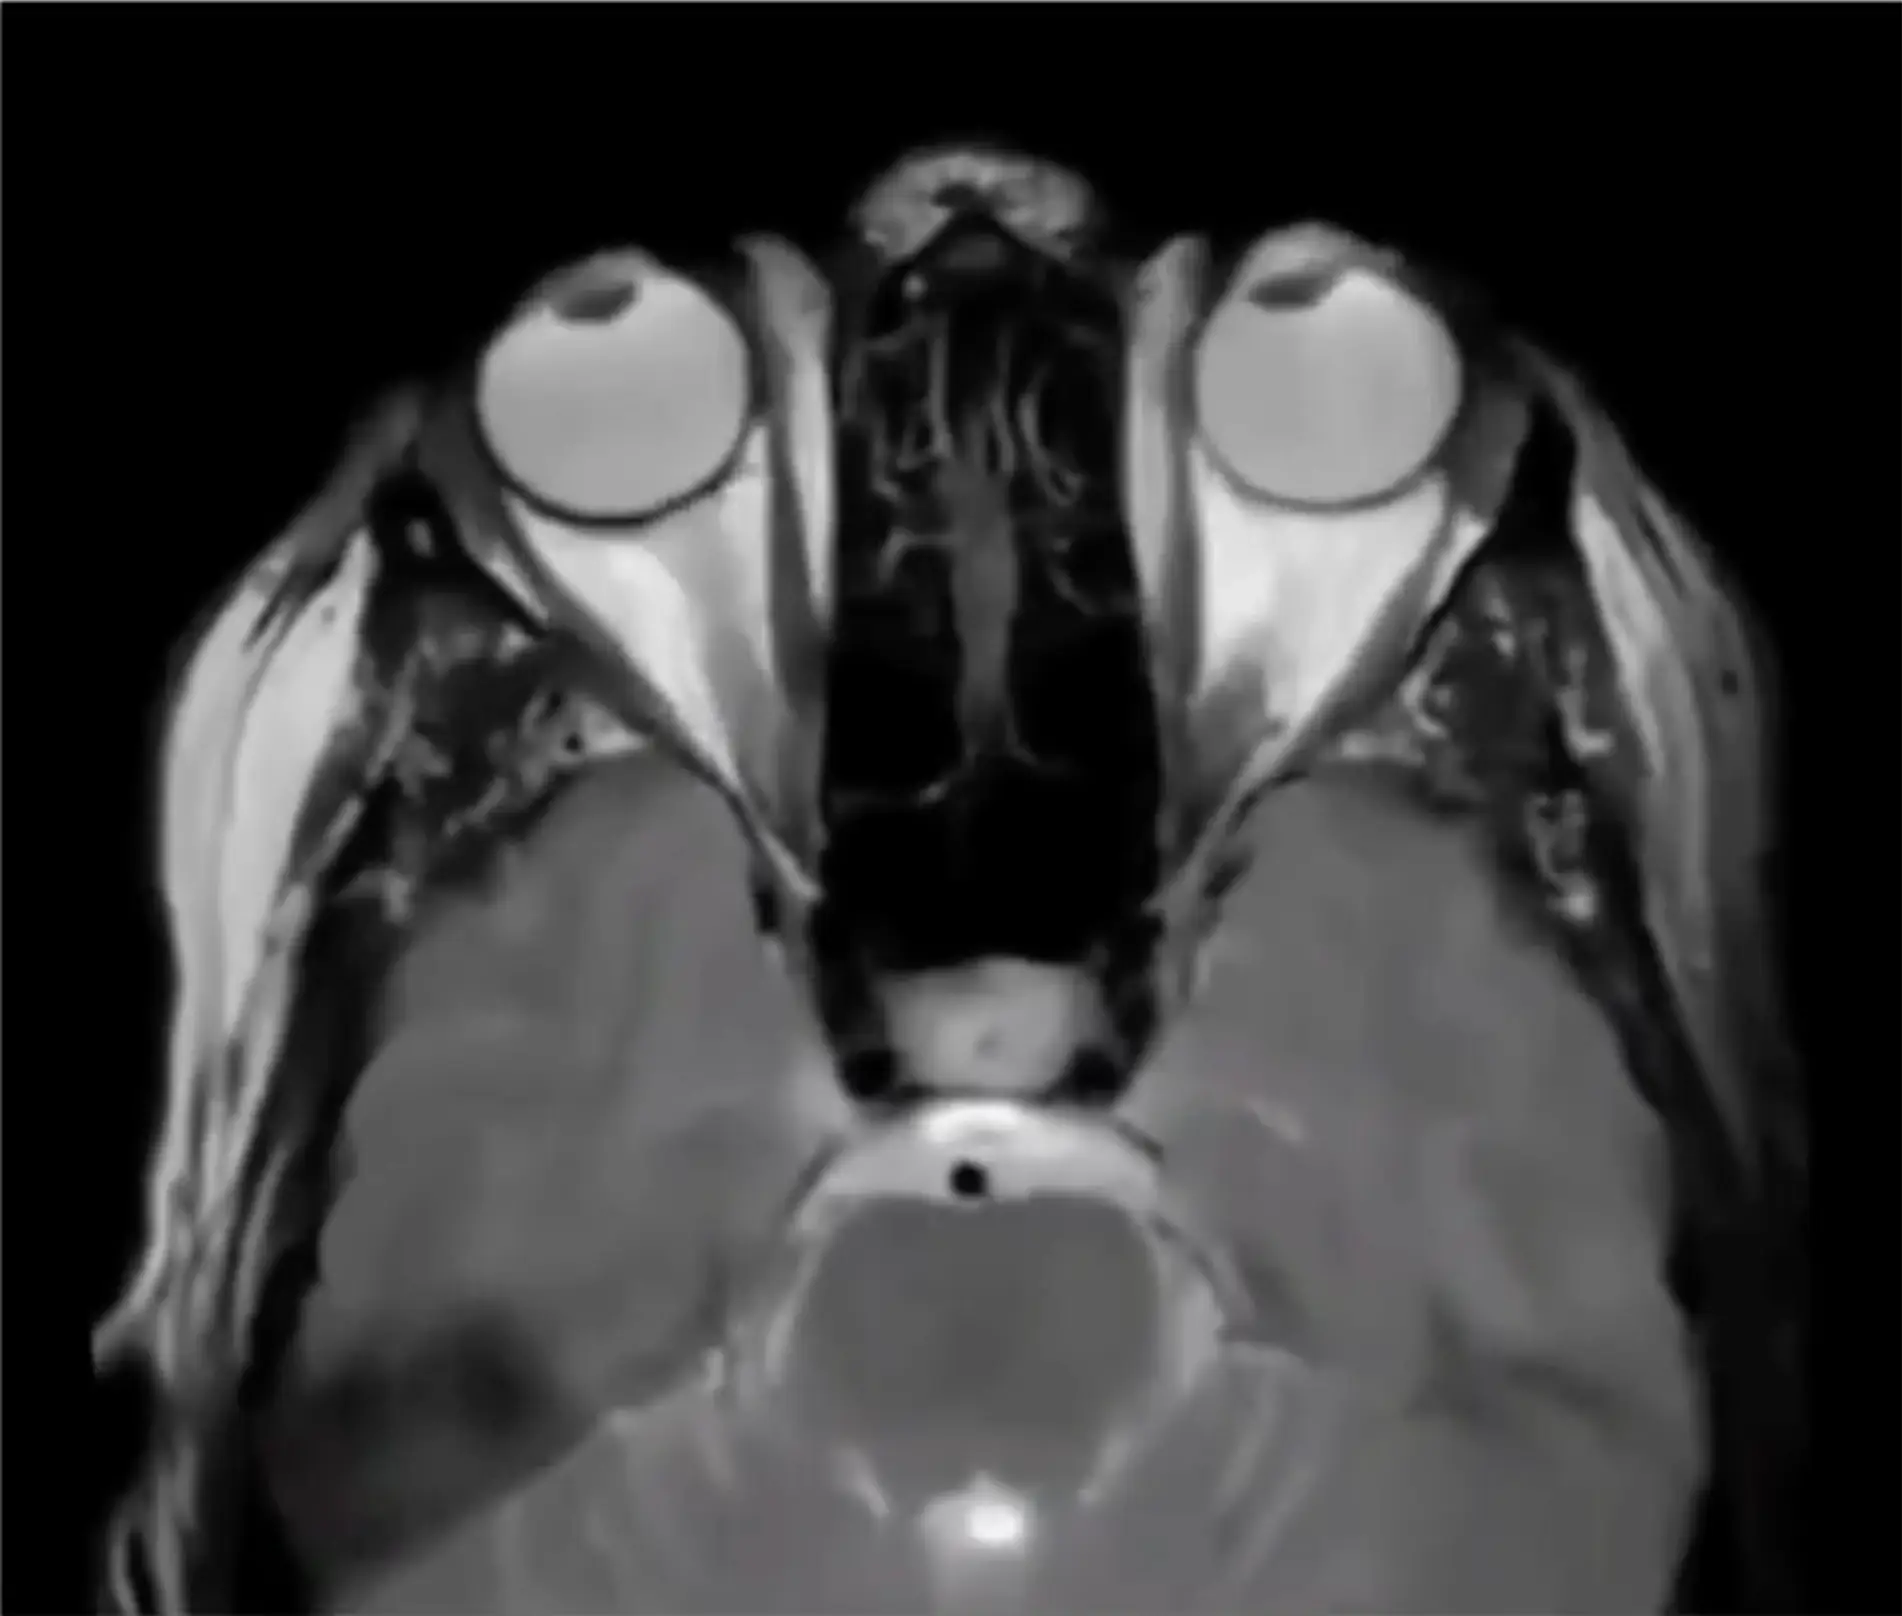

A video was uploaded onto Reddit which appears to show someone in REM sleep during an MRI scan.

In the clip, the unknown person’s eyes are moving rapidly back and forth in their sleep.